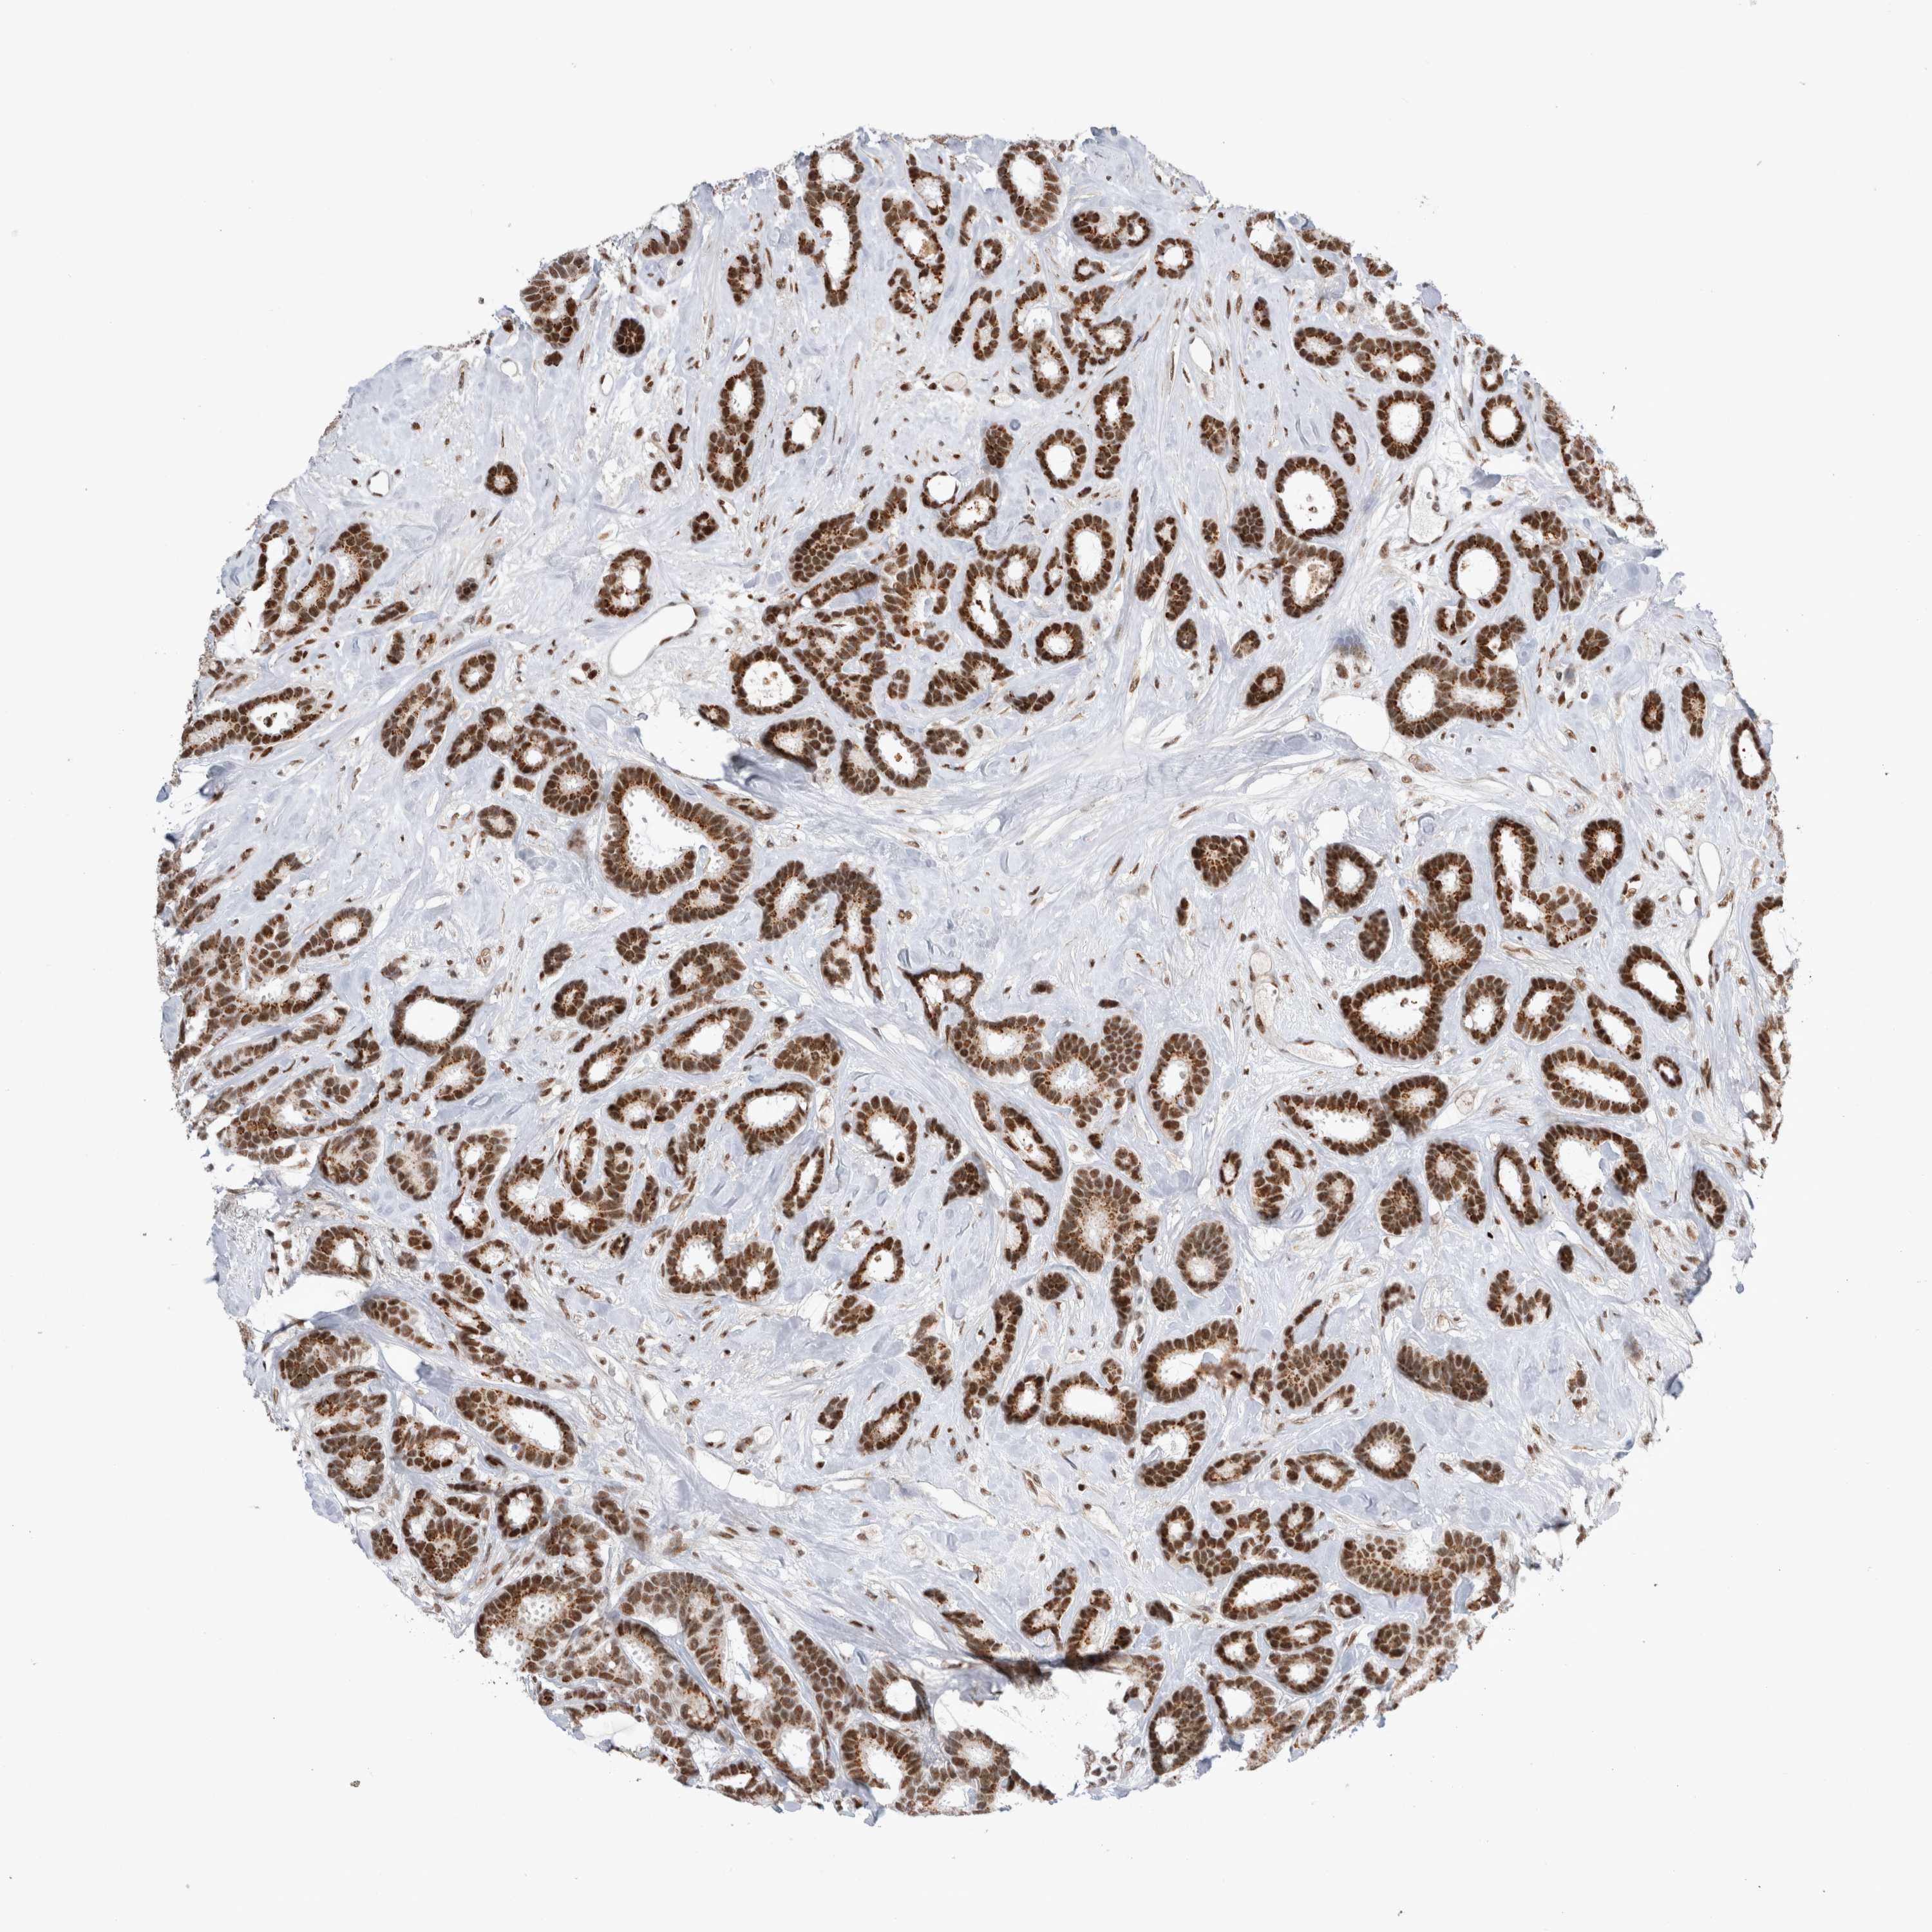

CANCER BREAST CANCER Show tissue menu

BRCA TCGA BRCA VALIDATION PROTEIN EXPRESSION